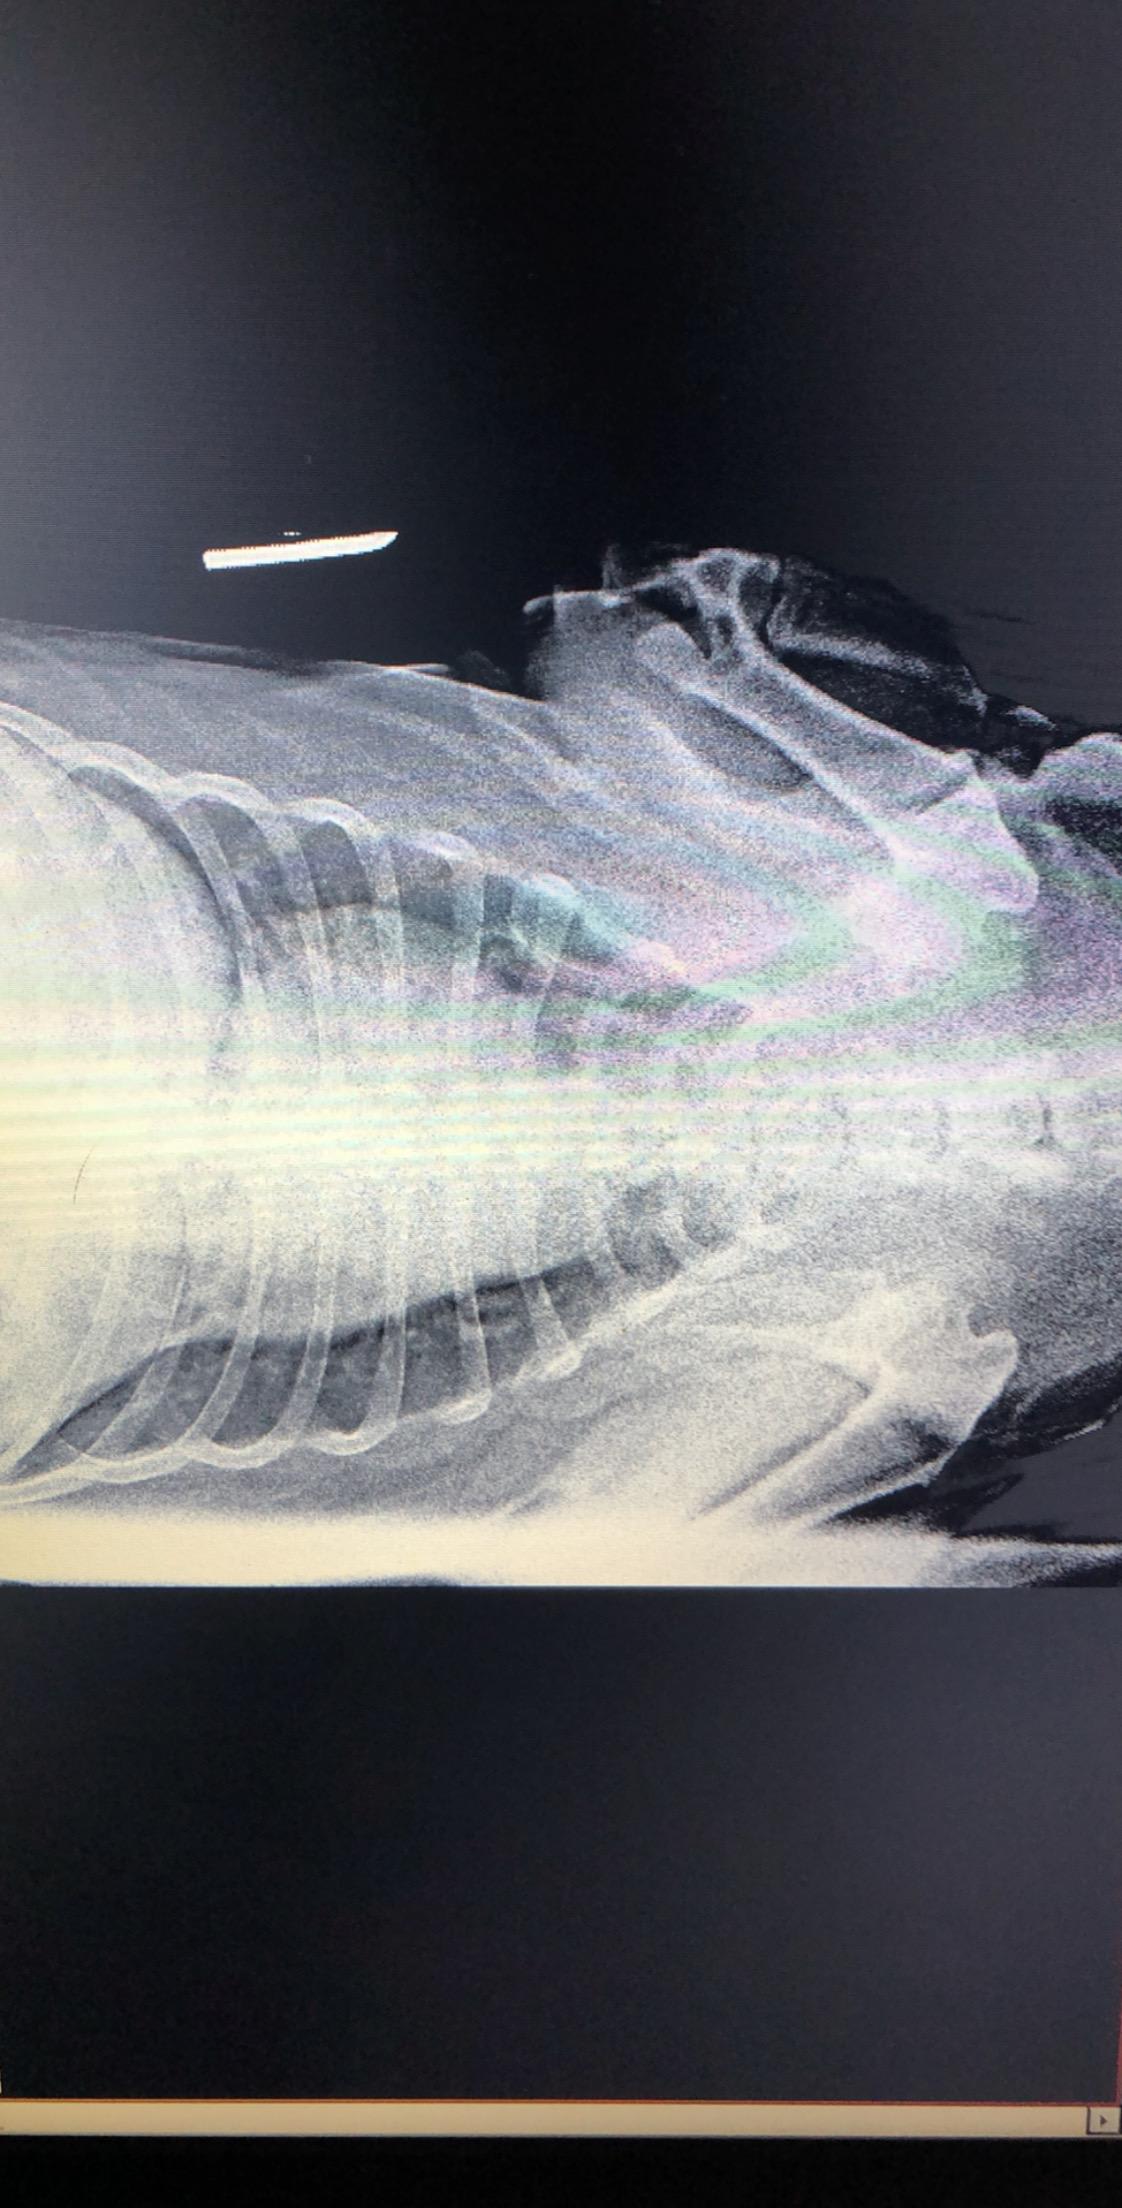

I took my 11 year old lab to the vet last night for coughing and vomiting clear liquid. The tested for pneumonia and Heartworm, both were negative. The vet seemed like he didn’t really know much about what was going on. He said her heart was enlarged and there was something going on with her lungs and maybe the liver, but refused to do any further testing. My question is, what do you think about these X-rays? Do you see anything that could be helpful in finding a diagnosis? Thanks in advance!

Hello and welcome to Petco Pet Education Center, formerly Petcoach. Coughing and bringing up clear liquid could be coughing up stuff instead of vomiting. This is important to try to differentiate. Coughing up liquid is more consistent with heart disease. The x-rays are difficult to read as the image transfer through is of poor quality and to really assess the lungs you need good quality images, however the heart does look a bit enlarged and the lungs do look a bit 'white'. I cannot assess the liver on these radiographs as you cannot see them. An enlarged heart, white lungs (fluid in the lungs), and an enlarged liver is consistent with both right and left sided heart disease. I recommend you return either to your vet, or another vet, and get a specialist ultrasound of the heart (an 'echo') to determine if heart medications are required. Your vet can also listen to the heart to see if a murmur is present in the heart, or 'crackles' are heard on the lungs. Heart disease is very serious and needs medications to manage. Without these Lily unfortunately will essentially drown in her own lungs, if heart disease is the problem. I suggest a recheck as soon as possible to get this figured out. Best of luck with Lily, I hope she feels better soon.